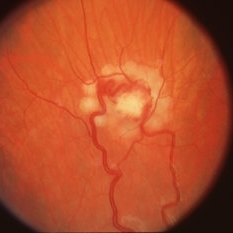

Retinal angioma OD in Von Hippel-Lindau.

Condition/keywords: retinal angioma, Von Hippel-Lindau